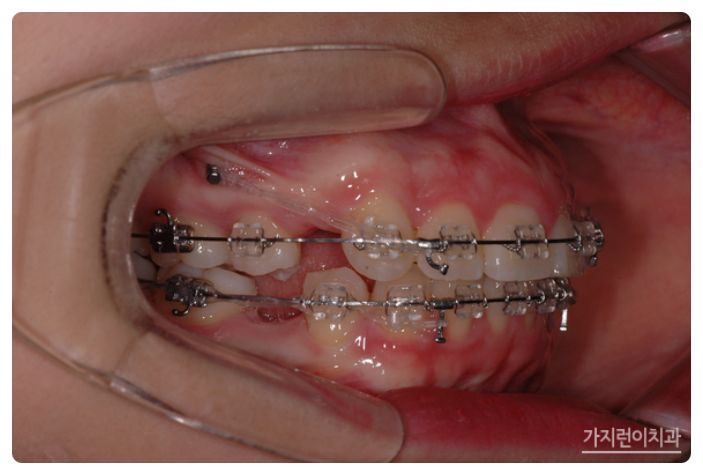

서울가지런이치과 교정과 의원, 강남에서도 거미스마일과 돌출입 치아교정이 이루어지고 있었는데요. 충분한 치아이동 공간을 확보하기 위해 상하악 1소구치를 발치한 후에 상악 잇몸뼈에 미니스크류를 식립해 효과적으로 힘을 주어 치아를 이동시켰습니다. 미니스크류를 진행하게 되면 상악 전치의 후방 이동이 일어나면서 상악 전치를 위로 합입시킬 수 있는데요. 상악이 어느 정도 이동한 것을 확인한 후에 하악에도 미니스크류를 식립해 상하악 전치를 동시에 후방으로 이동시킬 수 있었습니다.

약 1년 8개월 정도의 시간이 소요됐지만 환자분의 경우 거미스마일 교정과 더불어 돌출입 교정도 깨끗하게 진행이 되었는데요. 이처럼 교합면도 개선하고 돌출입과 잇몸이 많이 보이는 증상까지 개선해보니 안모 변화도 기대해볼 수 있었습니다.